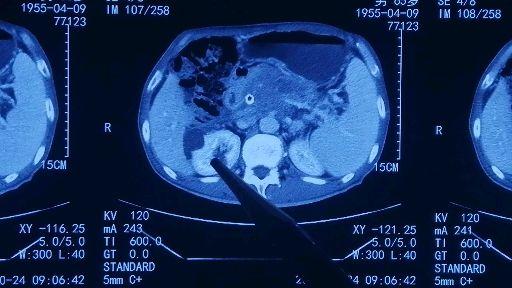

9.11腹部增强ct:肝右叶弥漫性肝癌

门诊行上腹部增强ct检查示:肝左叶,右叶多发异常强化影,考虑肝癌,afp

增强ct发现肝占位,提示肝癌

9.11腹部增强ct:肝右叶弥漫性肝癌,可见门脉癌栓